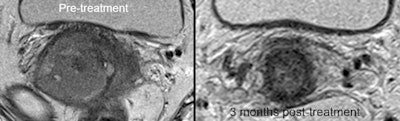

33-year-old LACC patient with stage 2B disease, node negative. MRI was performed 86 days after completion of conformal radiation therapy. Score grade 1 was recorded, indicating complete response. All images courtesy of Prof. Andy Scarsbrook. FDG-PET/CT in the same patient shows primary tumor, SUVmax 11.5. FDG-PET/CT scan performed 94 days after completion of CRT gave score of grade 4, indicating patient metabolic response.

FDG-PET/CT in the same patient shows primary tumor, SUVmax 11.5. FDG-PET/CT scan performed 94 days after completion of CRT gave score of grade 4, indicating patient metabolic response. MRI performed five months later showed local relapse. PET/CT confirmed this and showed no distant disease. Patient underwent salvage pelvic exenteration and was disease-free two years later.

MRI performed five months later showed local relapse. PET/CT confirmed this and showed no distant disease. Patient underwent salvage pelvic exenteration and was disease-free two years later.A total of 95 patients were included in the study. Of these, 21 (22%) had evidence of persistent local and/or nodal disease after CRT. The diagnostic performance of MRI (accuracy 77%, positive predictive value [PPV] 29%, negative predictive value [NPV] 84%) and PET/CT (accuracy 77%, PPV 27%, NPV 94%) was similar.